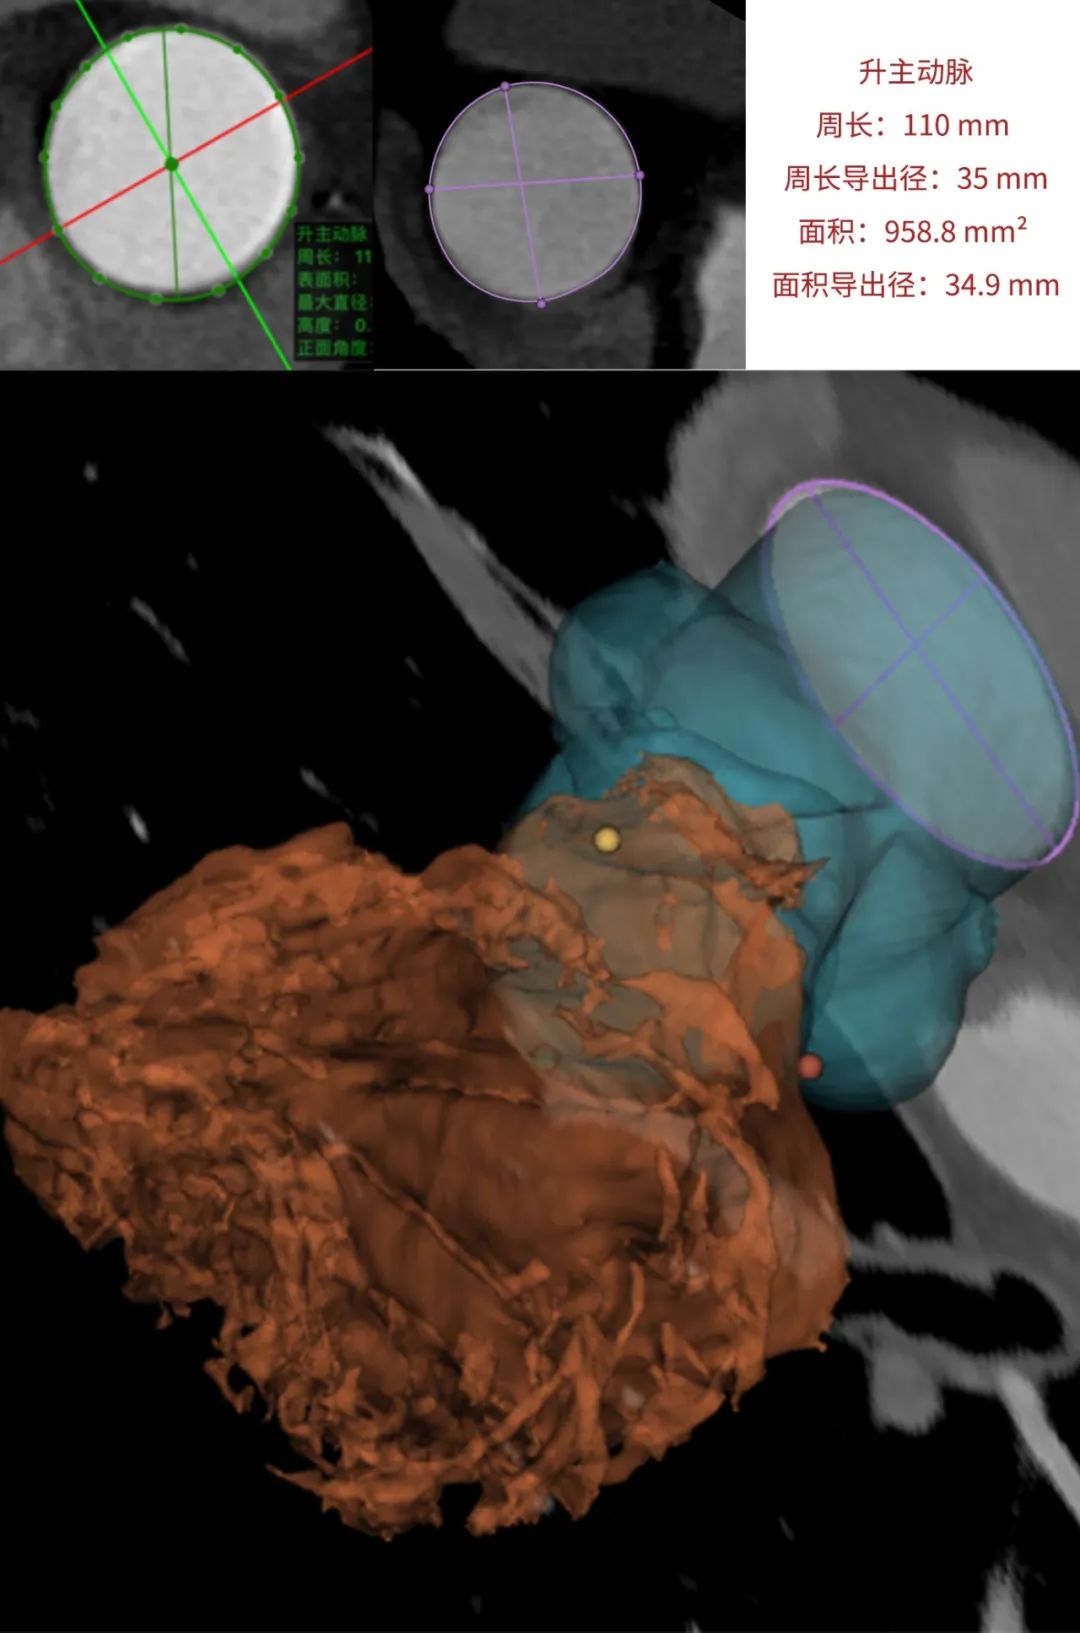

患者为68岁男性,因心悸胸闷入院。术前超声报告显示,患者为功能型二叶式主动脉瓣,右无融合钙化,主动脉瓣明显增厚钙化,瓣叶开放受限,主动脉瓣前向血流加速Vmax=4.2m/s,平均跨瓣压差36mmHg,有效开口面积0.7cm²,舒张期瓣口中度反流信号。

临床团队同时使用了基于医生手工描点的围术期影像评估软件和基于人工智能的瓣膜疾病围术期分析辅助决策软件进行术前影像学评估。

通过术前测量,对病例深入分析,结合人工智能术前分析辅助决策软件进行三维和二维图像融合,郭应强教授指出本例手术存在以下难点:

瓣叶明显增厚钙化,瓣膜释放过程中存在移位风险。

功能型二叶式主动脉瓣,瓣叶开口偏向一侧,瓣膜释放后存在不同轴可能。

患者不到70岁,需要考虑远期冠脉保护。

选择植入Xcor-26瓣膜,充分利用支撑臂避免瓣膜移位发生。

标准位释放,双锚定实现生理性同轴以获得更优的血流动力学效果。

在LAO 9 CAU 24(左右窦重合体位)投照角度,瓣叶交界贴合释放。